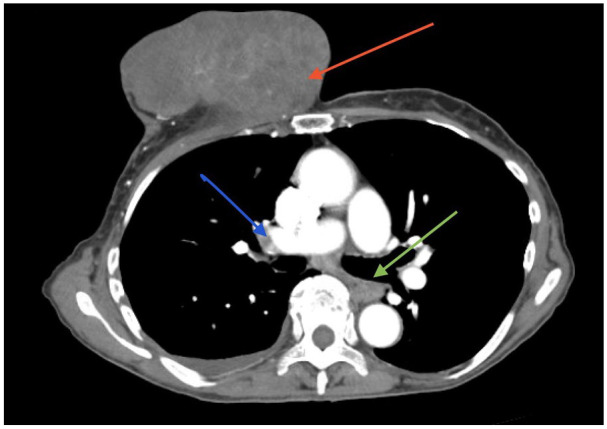

The introduction of screening mammograms has revolutionized the early detection of breast cancer. However, it remains the most common cancer in women in the United States, excluding skin cancer. As the incidence rates continue to rise, unusual presentations have become more frequent. Additionally, healthcare barriers can lead to delayed detection of breast cancer, resulting in unexpected complications. The occurrence of pyogenic liver abscess (PLA) in diabetic cancer patients, due to the synergistic effect of insulin-like growth factor-1 in tumorigenesis and abscess formation, is well documented. PLA is also prevalent in hepatocellular, colorectal, and pancreato-biliary tumors. However, the occurrence of PLA as an initial presentation of isolated advanced breast cancer without these comorbidities is understudied. This may be due to direct spread of infection from affected skin or spread via lymphatics or vasculature in the setting of immunosuppression from cancer. We present an exceedingly rare case of PLA, complicated by pulmonary embolism, in an elderly female with newly diagnosed stage IIIB breast carcinoma.